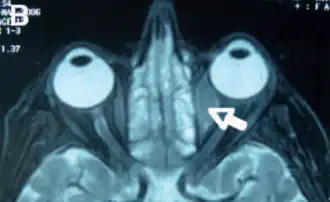

Орбитальная лимфома является распространенным типом неходжкинской лимфомы, что происходит вблизи глаза или в глазе. Общие симптомы включают в себя снижение зрения и увеит. Орбитальная лимфома может быть диагностирована с помощью биопсии глаза и обычно лечится с помощью лучевой терапии или её комбинации с химиотерапией.

Основные видимые симптомы глазной лимфомы включают экзофтальм и видимую массу в глазе. Другие симптомы связаны с масс-эффектом.